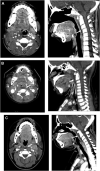

Figures